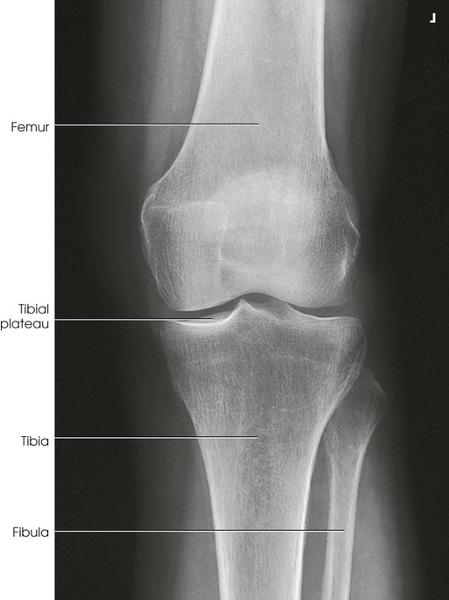

Structures

Shown

• Open knee joint

• Patella superimposed on

femur

• Soft tissue

AP of the Knee